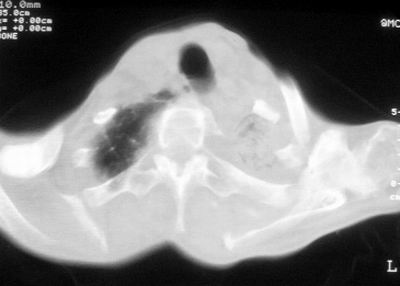

患者,男,47岁,反复咳嗽、咯痰、咯血3年,再发5天。痰培养未找到真菌、抗酸杆菌、癌细胞。

以下是引用xulianj在2008-2-25 21:01:00的发言:[br]左肺上叶结核伴肺纤维化有霉菌球形成,纵隔移位,左肺下叶感染性病变,建议抗炎抗结核后复查,双肺气肿.

考虑:左肺慢纤伴霉菌球形成、双肺全小叶型肺气肿。

1)考虑为:左肺上叶肺结核(空洞形成),伴左下肺感染;不排除霉菌感染可能。2)肺气肿。

左肺上叶结核伴肺纤维化空洞形成并左肺下叶感染,纵隔牵拉移位,建议作进一步检查排除左侧肺霉菌感染可能。